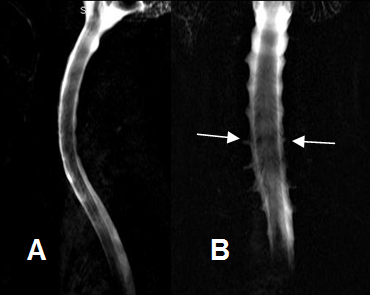

Fig 5. Raíces normales.

A: RM sagital en T1 y B: RM sagital en T2. Raíces normales (Flechas delgadas), por encima de los vasos subclavios. (Flechas gruesas).